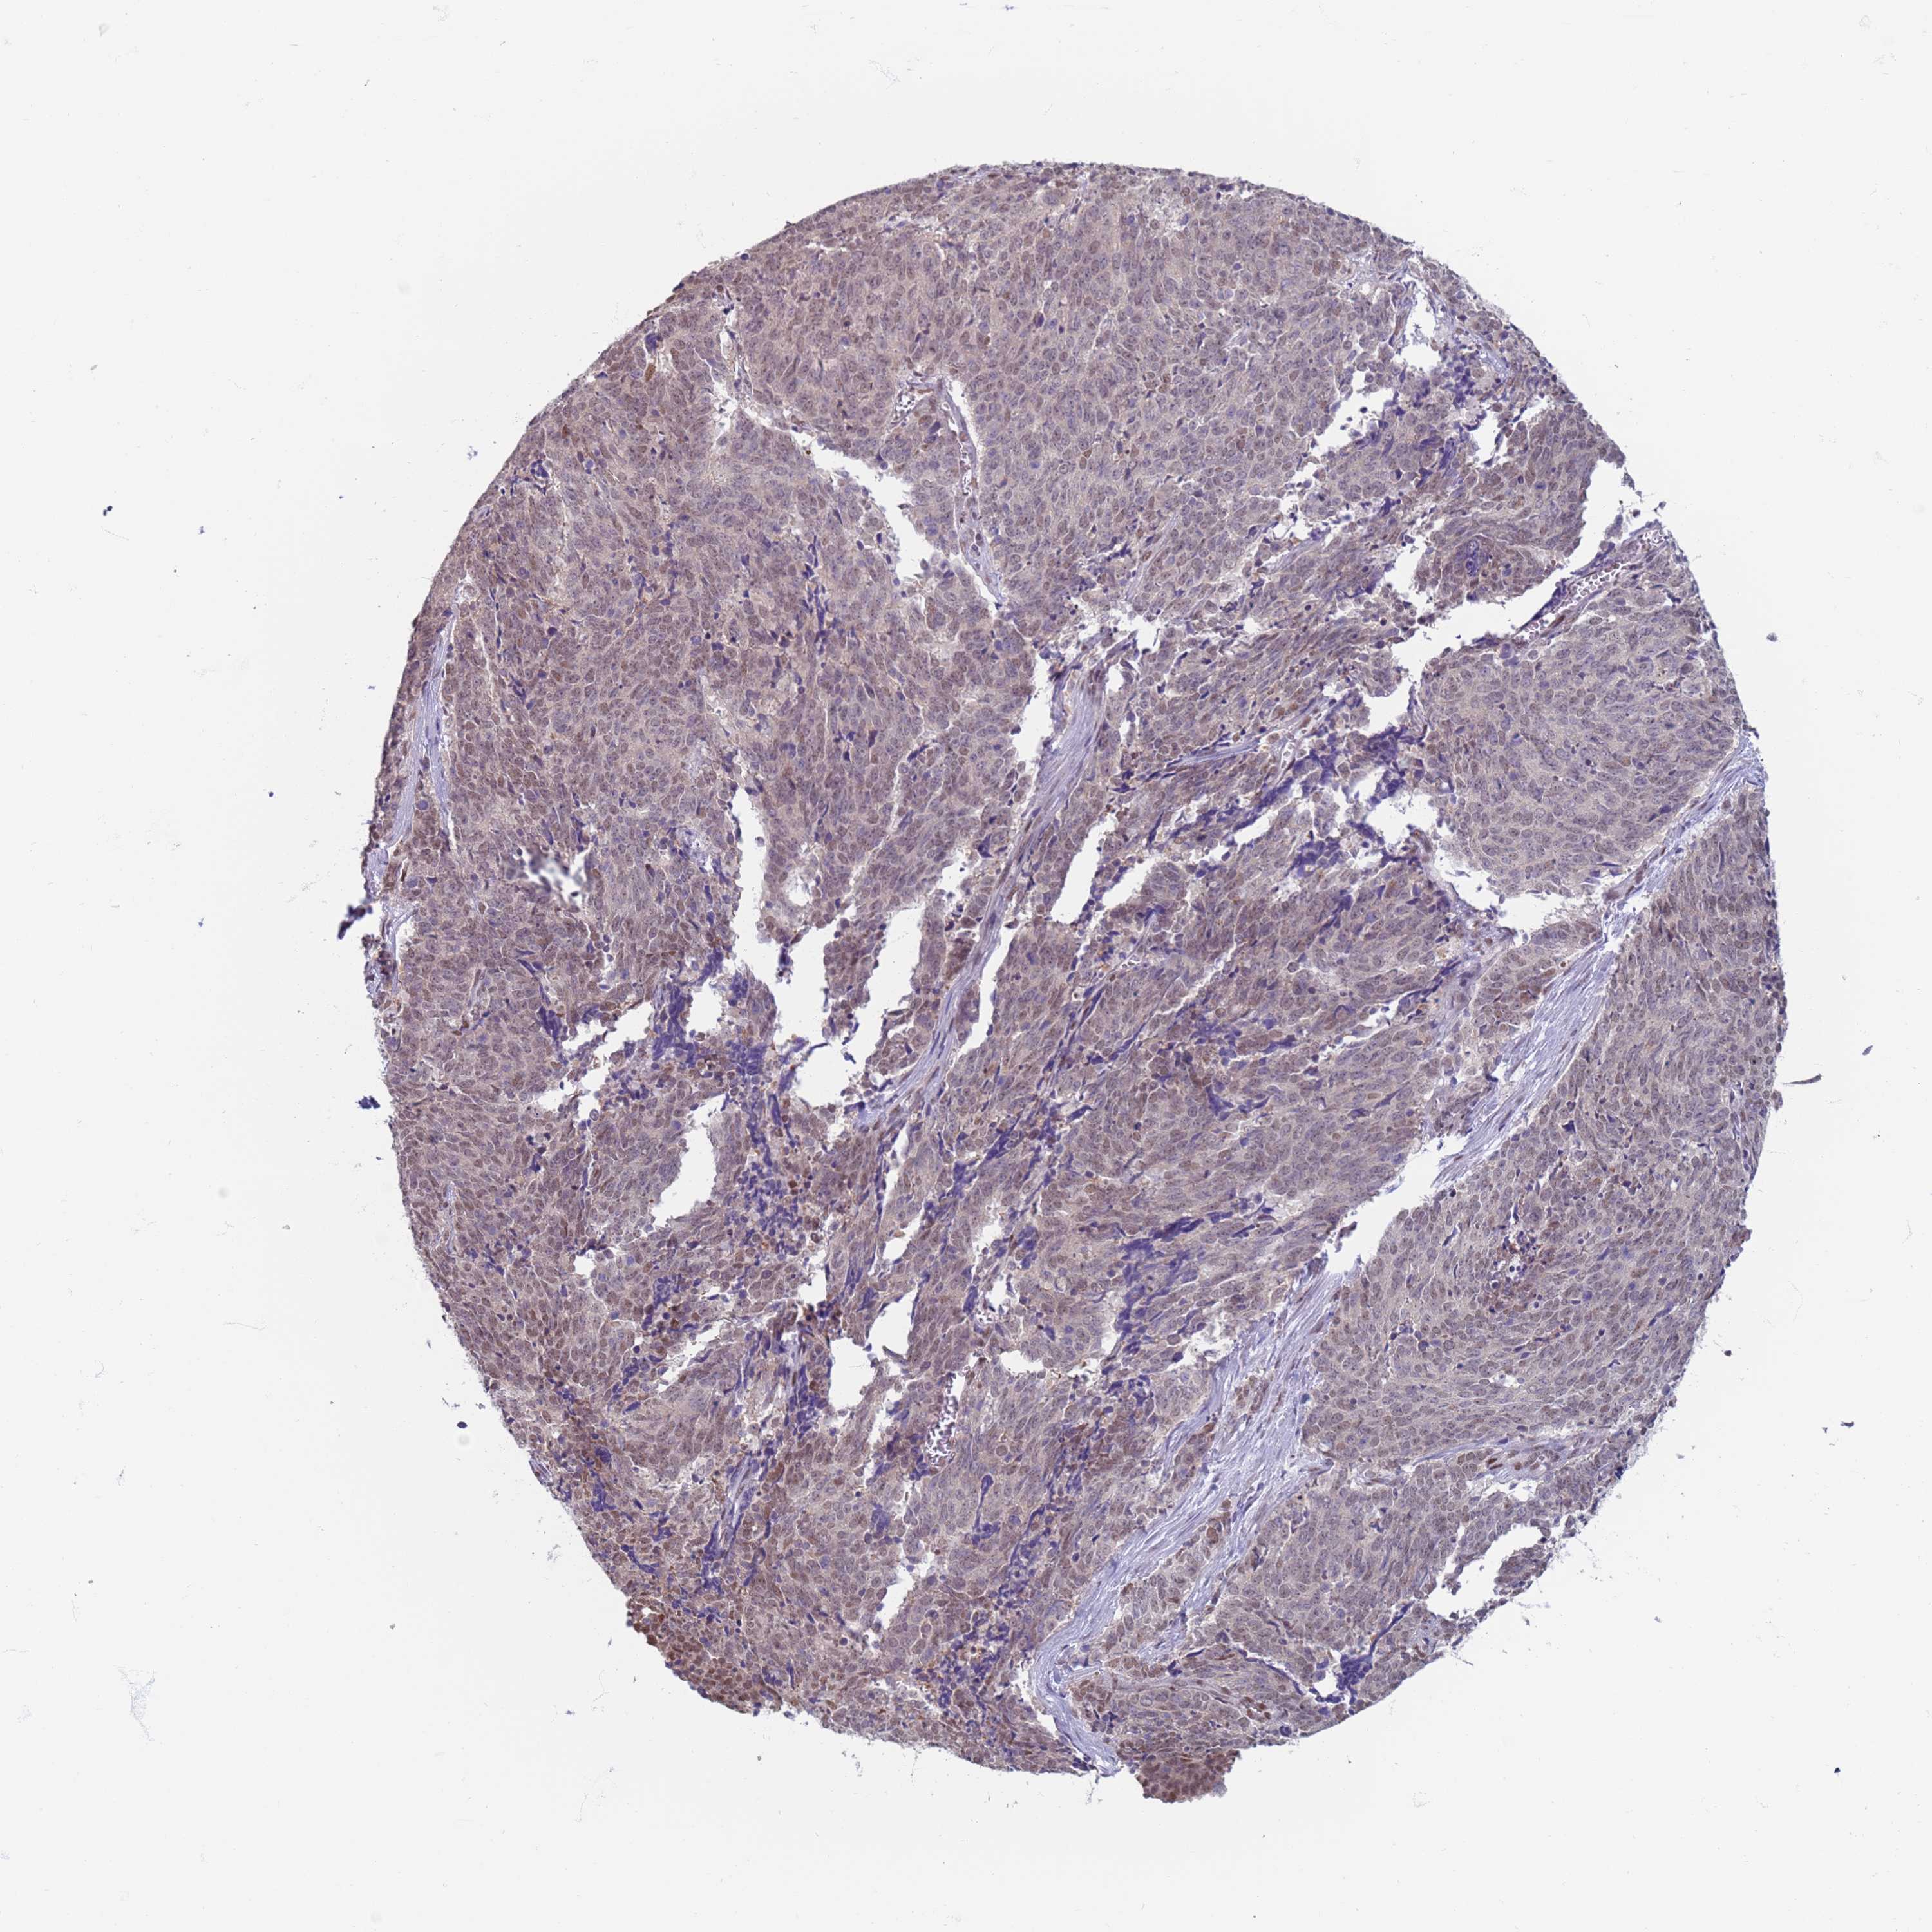

CERVICAL CANCER - Protein expressioni

A mouse-over function shows sample information and annotation data. Click on an image to view it in a full screen mode. Samples can be filtered based on level of antibody staining by selecting one or several of the following categories: high, medium, low and not detected. The assay and annotation is described here.

Note that samples used for immunohistochemistry by the Human Protein Atlas do not correspond to samples in the TCGA dataset.

Antibody stainingi

Antibody staining in the annotated cell types in the current human tissue is reported as not detected, low, medium, or high, based on conventional immunohistochemistry profiling in selected tissues. This score is based on the combination of the staining intensity and fraction of stained cells.

Each image is clickable and will lead to virtual microscopy that enables deeper exploration of all samples and also displays staining intensity scores, fraction scores and subcellular localization as well as patient and tissue information for each sample.

Antibody HPA041906

Antibody HPA043552

Staining

High

Medium

Low

Not detected

Intensity

Strong

Moderate

Weak

Negative

Quantity

>75%

75%-25%

<25%

None

Location

Nuclear

Cytoplasmic/membranous

Cytoplasmic/membranous,nuclear

Squamous cell carcinoma, NOS

Adenocarcinoma, NOS